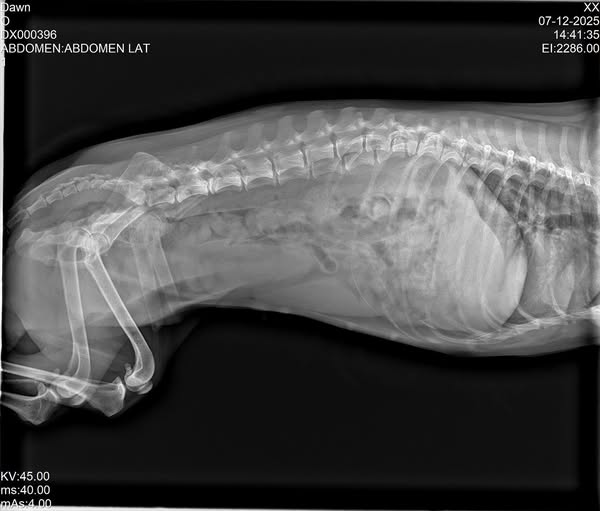

Patient was brought to the clinic with a concern of extended menstrual cycle, upon physical examination and series of laboratory tests it turned out to be a case of "PYOMETRA"

Pyometra is a secondary infection due to hormonal changes in a female's reproductive tract. If pregnancy does not occur for several estrous cycles, the lining increases in thickness until cysts form in the uterus. The thickened cystic lining secretes fluids, creating an ideal environment where bacteria can grow.

Pyometra is a serious and life-threatening infection in the uterus. The condition must be treated quickly and aggressively.